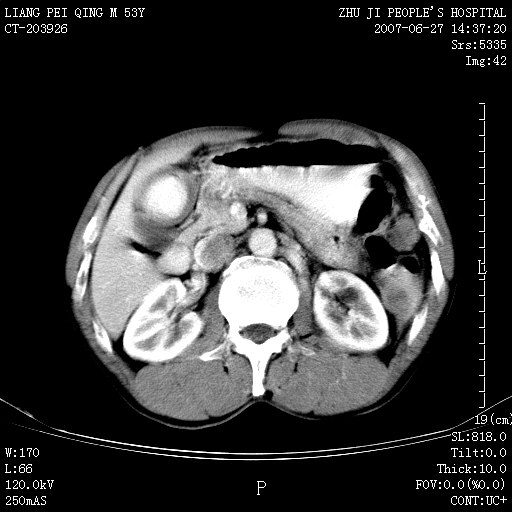

以下是引用余辉在2007-6-27 18:46:00的发言:[br]病灶多发,内可见大片状低密度区,病灶病灶等密度区轻度强化,动脉期后期病灶低密度区与高密度区对度增加,考虑1淋巴瘤2转移瘤3血管内皮细胞瘤(不知有否静脉期及延迟期扫描)

以下是引用zzzzhhhhaaaannnn在2007-6-27 20:44:00的发言:[br]脾脏 肋骨转移可能性大,下腔静脉内有癌栓

以下是引用狙击手在2007-6-28 10:35:00的发言:[br]1:定位:来源于脾脏。2:强化:强化,但不均匀。3:下腔静脉癌栓?下腔静脉充填不均匀与增强时间有关,延时即可明确。4:肋骨破坏?看起来并不确切。综上考虑几个最常见诊断:1;淋巴管瘤;2;血管内皮肉瘤(高度恶性,早期即可转移,常见肝,肺,骨)3;转移瘤(无特征性,只有肝或其它腹腔脏器有类似病变时,才可提示之)